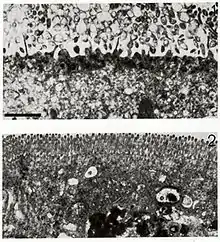

Rotaviruses replicate mainly in the gut,[77] and infect enterocytes of the villi of the small intestine, leading to structural and functional changes of the epithelium.[78] There is evidence in humans, and particularly in animal models of extraintestinal dissemination of infectious virus to other organs and macrophages.[79]

The diarrhoea is caused by multiple activities of the virus.[80] Malabsorption occurs because of the destruction of gut cells called enterocytes. The toxic rotavirus protein NSP4 induces age- and calcium ion-dependent chloride secretion, disrupts SGLT1 (sodium/glucose cotransporter 2) transporter-mediated reabsorption of water, apparently reduces activity of brush-border membrane disaccharidases, and activates the calcium ion-dependent secretory reflexes of the enteric nervous system.[56] The elevated concentrations of calcium ions in the cytosol (which are required for the assembly of the progeny viruses) is achieved by NSP4 acting as a viroporin. This increase in calcium ions leads to autophagy (self destruction) of the infected enterocytes.[81]

Healthy enterocytes secrete lactase into the small intestine; milk intolerance due to lactase deficiency is a symptom of rotavirus infection,[84] which can persist for weeks.[85] A recurrence of mild diarrhoea often follows the reintroduction of milk into the child's diet, due to bacterial fermentation of the disaccharide lactose in the gut.[86]